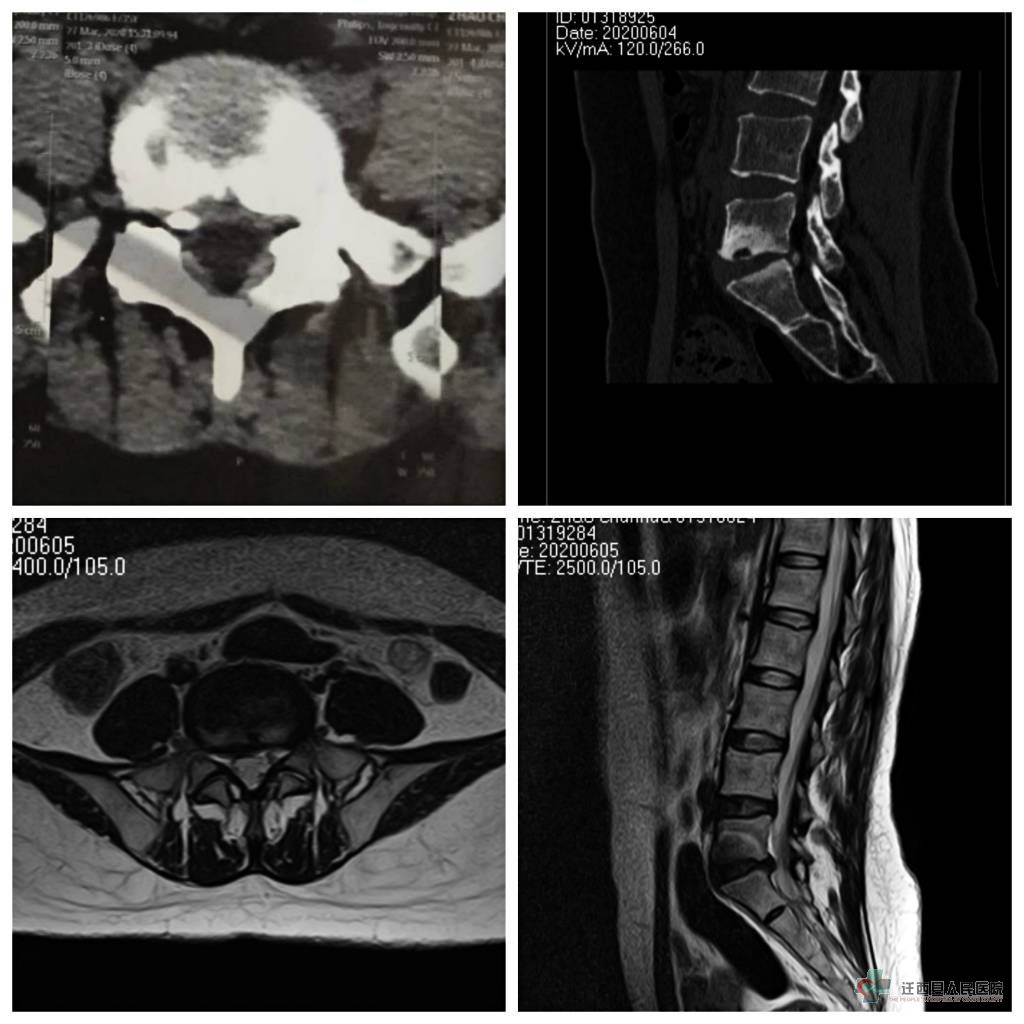

(患者术前CT及核磁影像)

2020年5月30日,35岁的患者赵女士,主因腰部疼痛伴右下肢疼痛、足背麻木3个月加重一周到迁西县人民医院骨科就诊。核磁检查显示:腰5骶1椎间盘突出伴钙化(右后侧),压迫脊神经。入院诊断:腰5骶1椎间盘突出症。 据赵女士介绍,来院前她曾到外院诊治,外院建议她进行外科手术治疗。但是面对开放手术,赵女士和家人都非常恐惧,于是抱着试试看的态度来到了迁西县人民医院。 赵女士入院后,该院骨科专家团队进行了充分分析讨论与评估,认为其病情完全符合微创手术适应症,在与患者及家属沟通后,决定为患者选择当下最前沿的微创手术—椎间孔镜下腰椎间盘突出致压物摘除+射频消融术,进行治疗。手术过程顺利,术后患者恢复效果良好,下床活动自如,第三日即出院。